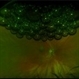

- Diabetic Tractional Detachment

- Angela Rico M.D.

- Imaging device

- Fundus camera

- 42 y/o Diabetic BM with Tractional Diabetic RD